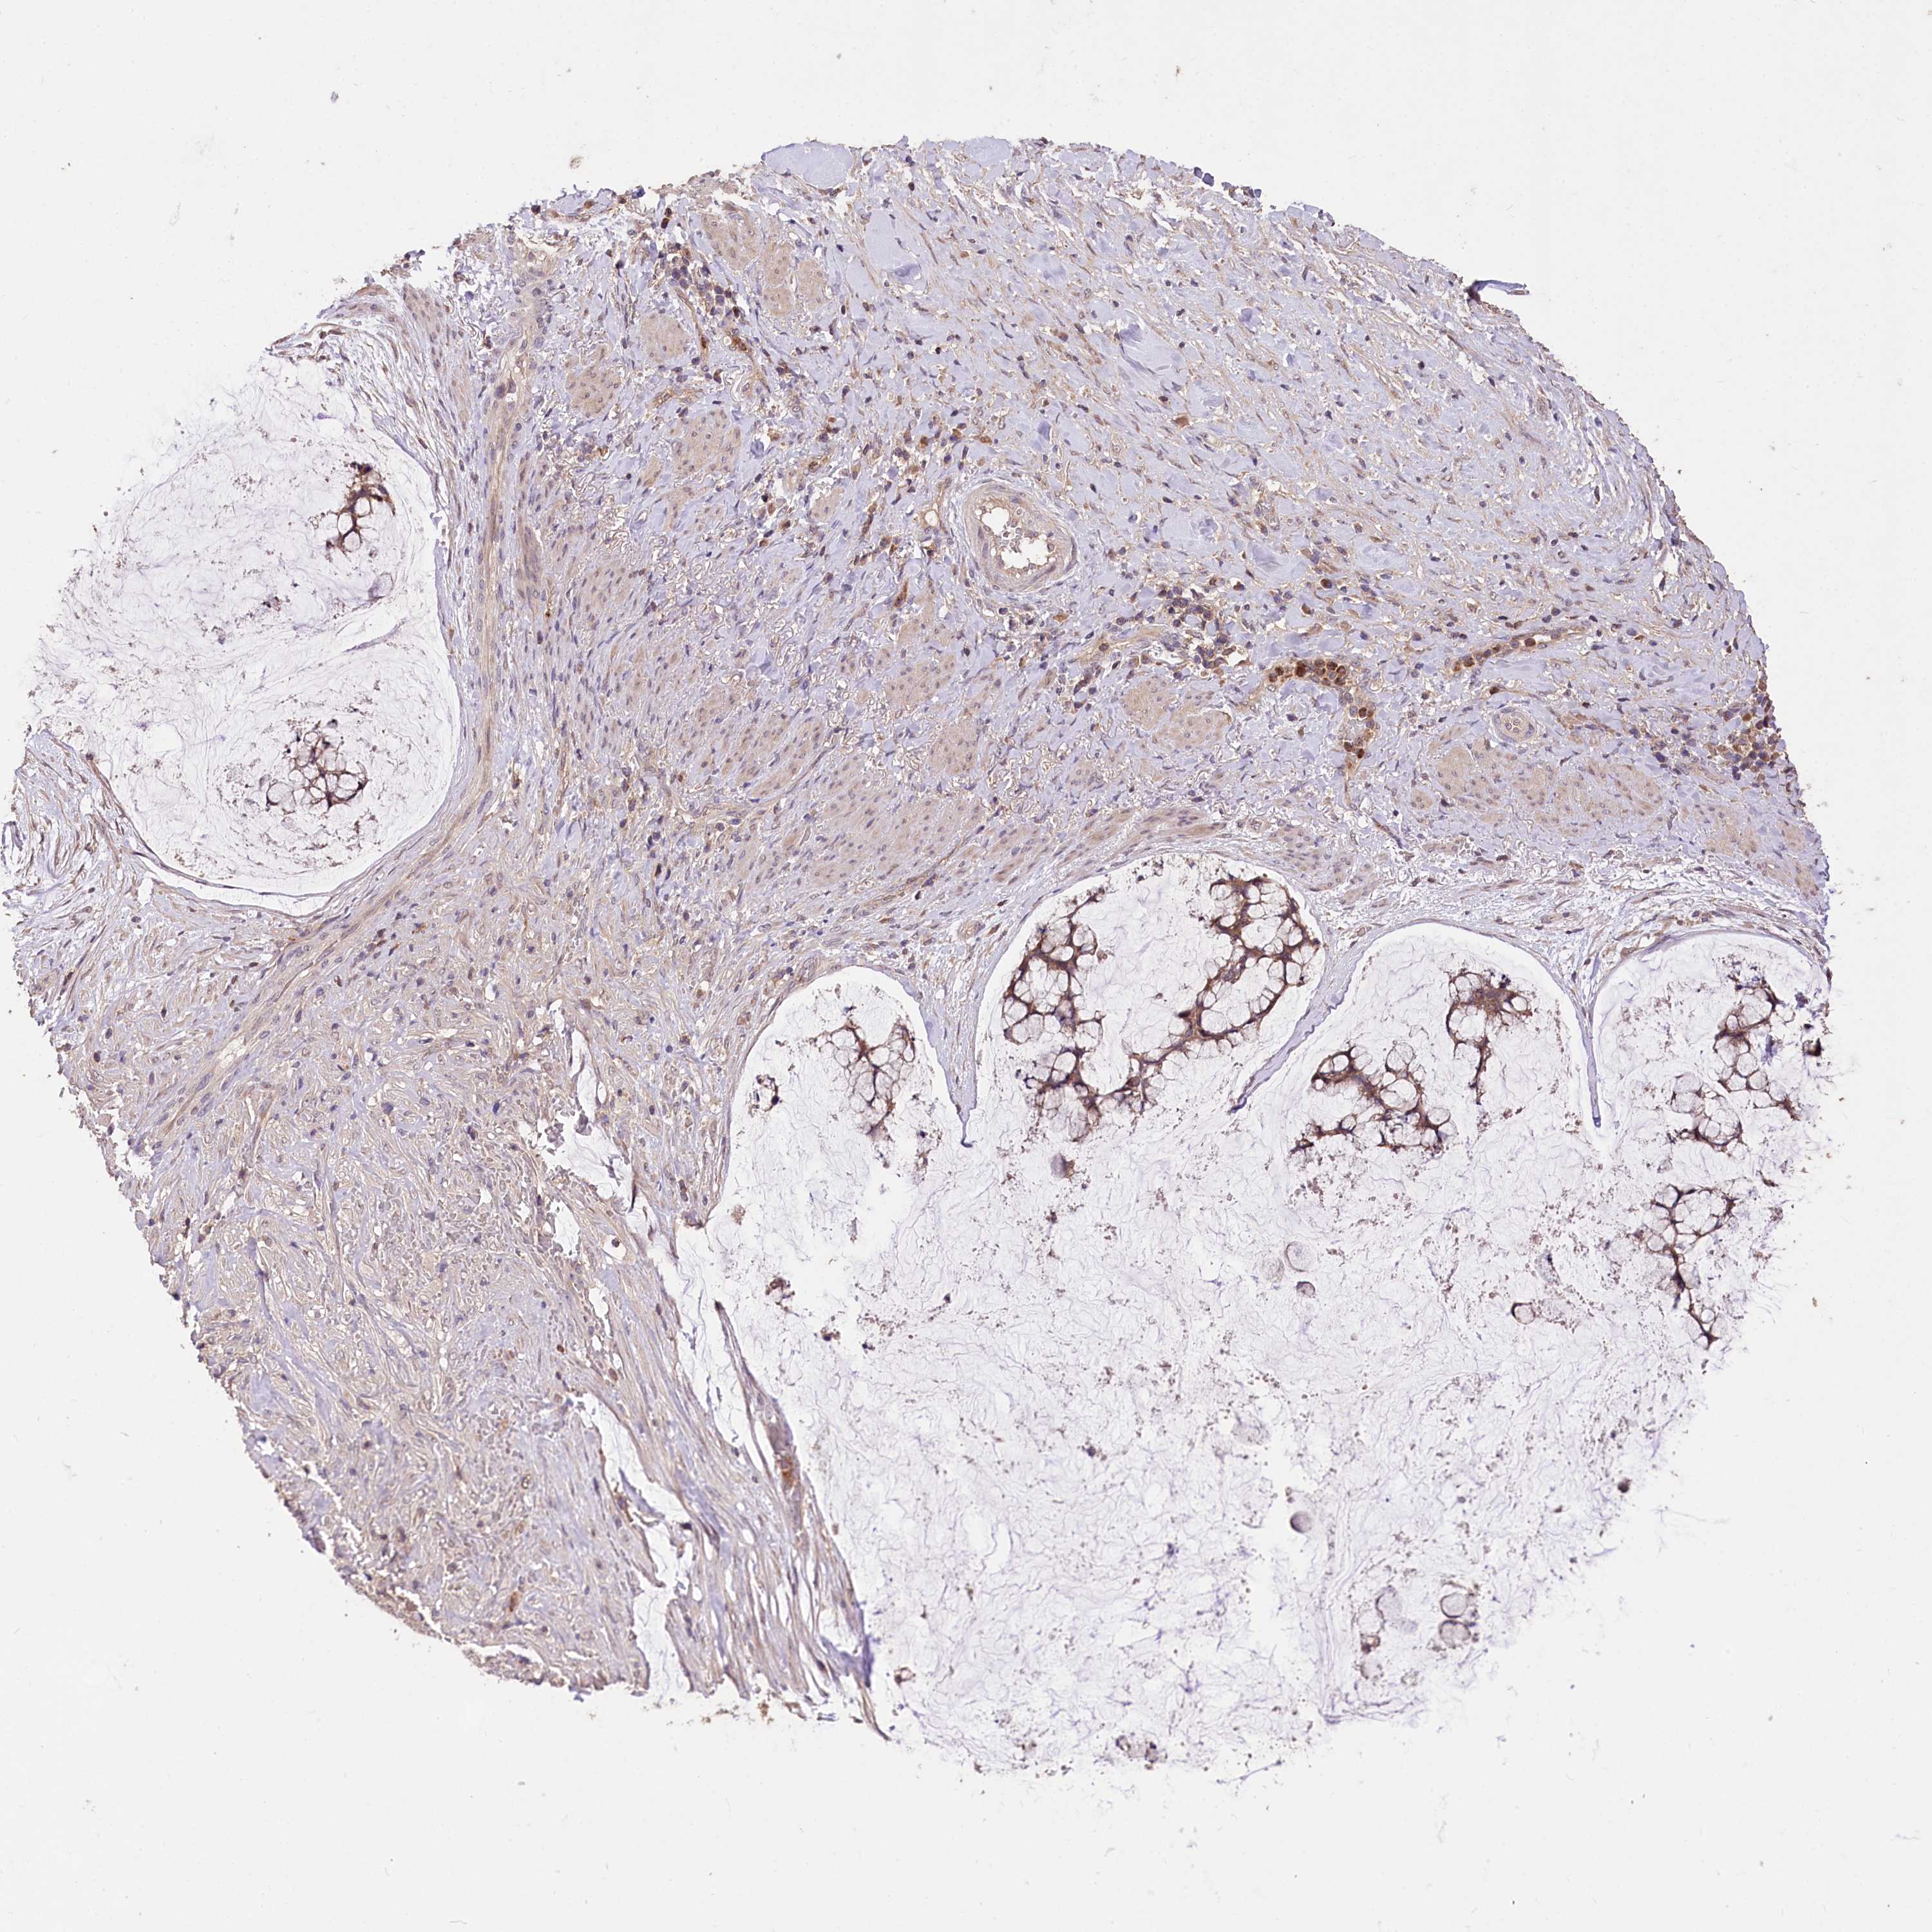

OVARIAN CANCER - Protein expressioni

A mouse-over function shows sample information and annotation data. Click on an image to view it in a full screen mode. Samples can be filtered based on level of antibody staining by selecting one or several of the following categories: high, medium, low and not detected. The assay and annotation is described here.

Note that samples used for immunohistochemistry by the Human Protein Atlas do not correspond to samples in the TCGA dataset.

Antibody stainingi

Antibody staining in the annotated cell types in the current human tissue is reported as not detected, low, medium, or high, based on conventional immunohistochemistry profiling in selected tissues. This score is based on the combination of the staining intensity and fraction of stained cells.

Each image is clickable and will lead to virtual microscopy that enables deeper exploration of all samples and also displays staining intensity scores, fraction scores and subcellular localization as well as patient and tissue information for each sample.

Antibody HPA037811

Antibody HPA037812

Staining

High

Medium

Low

Not detected

Intensity

Strong

Moderate

Weak

Negative

Quantity

>75%

75%-25%

<25%

None

Location

Nuclear

Cytoplasmic/membranous

Cytoplasmic/membranous,nuclear

Carcinoma, endometroid

Cystadenocarcinoma, mucinous, NOS

Carcinoma, NOS